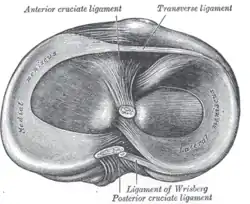

Menisken

Da die miteinander in Verbindung stehenden (artikulierenden) Gelenkflächen nicht genau aufeinander passen, wird diese „Ungleichheit“ (Inkongruenz) durch halbmondförmige Faserknorpelscheiben, die Menisken ausgeglichen, die den Drehbewegungen folgen können. Eine weitere Aufgabe der Menisken besteht in der Vergrößerung der Kontaktfläche zwischen Schienbein und Oberschenkelknochen.

Man unterscheidet einen Innenmeniskus (Meniscus medialis), der C-förmig, größer und etwas unbeweglicher (da mit dem Innenband verwachsen) ist, und einen Außenmeniskus (Meniscus lateralis), der kreisförmig, kleiner und beweglicher ist (da er mit keinem Seitenband verwachsen ist). Die Menisken sind im Querschnitt keilförmig. Die hohe Kante liegt außen, die niedrige innen. Da die Oberschenkelknochen genau in der Mitte direkt auf dem Schienbeinplateau und peripher auf den Menisken aufliegen, tragen diese einen wesentlichen Teil der Last.

Beim Bewegen des Kniegelenks werden die Menisken von den Oberschenkelkondylen (auch: 'Oberschenkelknorren', abgeleitet von „Baumstumpf“ oder „Holzklotz“, siehe auch: Oberschenkelknochen) vor sich her geschoben: Bei Beugung rollen und gleiten die beiden Kondylen zurück und drängen die Menisken nach hinten, bei Streckung gelangen sie wieder nach vorne. Bei Auswärtsdrehung des Unterschenkels wird der Außenmeniskus auf dem Schienbein nach vorne geschoben, der Innenmeniskus zurückgezogen, bei der Einwärtsdrehung ist es umgekehrt.

Die Menisken können vorne durch ein kurzes, kräftiges Band (Ligamentum transversum genus) verbunden sein, das aber variabel ist und keine Verbindung zum Schienbeinplateau hat. Als eigentliche Verankerung der Menisken strahlen die Fasern der Vorder- und Hinterhörner in das Schienbeinplateau ein und begründen damit die beträchtliche Zugfestigkeit. Zusätzlich können variabel angelegte Bänder (Ligamenta meniscofemoralia) den lateralen Meniskus mit dem inneren Oberschenkelknorren verbinden.[10]

Die Kreuzbänder (Ligamenta cruciata) ziehen von der Grube zwischen den Oberschenkelknorren zum Schienbein. Von der Seite und von vorn betrachtet überkreuzen sie sich dabei in ihrem Verlauf.

Vorderes Kreuzband

Das vordere Kreuzband (Ligamentum cruciatum anterius – bei Tieren Ligamentum cruciatum craniale) zieht von der vorderen Einmuldung zwischen den Schienbeinknorren zur Seite und etwas nach hinten, um an der Innenseite des seitlichen Oberschenkelknochens anzusetzen. Dabei teilt es sich in ein vorne-mittiges und in ein hinten-seitliches Bündel auf. Durch die weite Fächerung der Ursprungsfläche dieser Bündel ist sowohl bei Beugung, als auch bei Streckung ein Teil des vorderen Kreuzbandes gespannt. Dadurch verhindert es bei ausgestrecktem Bein eine Überstreckung (Hyperextension), während es bei Beugung dem Vorschub des Schienbeines entgegenwirkt („vordere Schublade“).

Hinteres Kreuzband

Das hintere Kreuzband (Ligamentum cruciatum posterius – bei Tieren Ligamentum cruciatum caudale) ist kräftiger und hat seinen Ursprung in der hinteren Einmuldung des Schienbeinplateaus und zieht nach vorne-mittig, um an der seitlichen Vorderfläche des inneren Oberschenkelknochens anzusetzen. Es spannt sich bei Beugung und verhindert damit ein nach hinten gerichtetes Weggleiten des Schienbeines (hintere Schublade). Bei ausgestrecktem Bein unterstützt das hintere Kreuzband das vordere beim Vorbeugen einer Überstreckung. Seine Hauptaufgabe ist jedoch die Stabilisierung des Knies bei Beugung und unter Last.